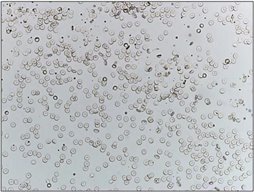

第二步:确诊与形态分析 - 尿沉渣显微镜检查

这是诊断血尿的 “金标准”。

· 红细胞计数:检验人员会直接计数视野中的红细胞数量。

· 正常参考值:通常为 0-3个/HPF(每高倍镜视野)。当红细胞 > 3个/HPF,即可诊断为“镜下血尿”。

· 红细胞形态:这是判断出血来源的关键!

· 正常形态红细胞:红细胞看起来和血液里的差不多,呈双凹圆盘状。这通常提示出血来自肾后性(肾盂、输尿管、膀胱、尿道),如结石、肿瘤、感染。

· 异形红细胞:包括大红细胞、小红细胞、棘细胞、球状凸起样红细胞、皱缩红细胞、环形红细胞、影红细胞等。由于红细胞挤过破损的肾小球滤过膜而变得奇形怪状,如大小不一、表面起泡、皱缩、破损等。这高度提示出血来自肾小球本身,是诊断肾小球性疾病的重要线索。

· 混合型:两者兼有,需要进一步甄别血尿来源。